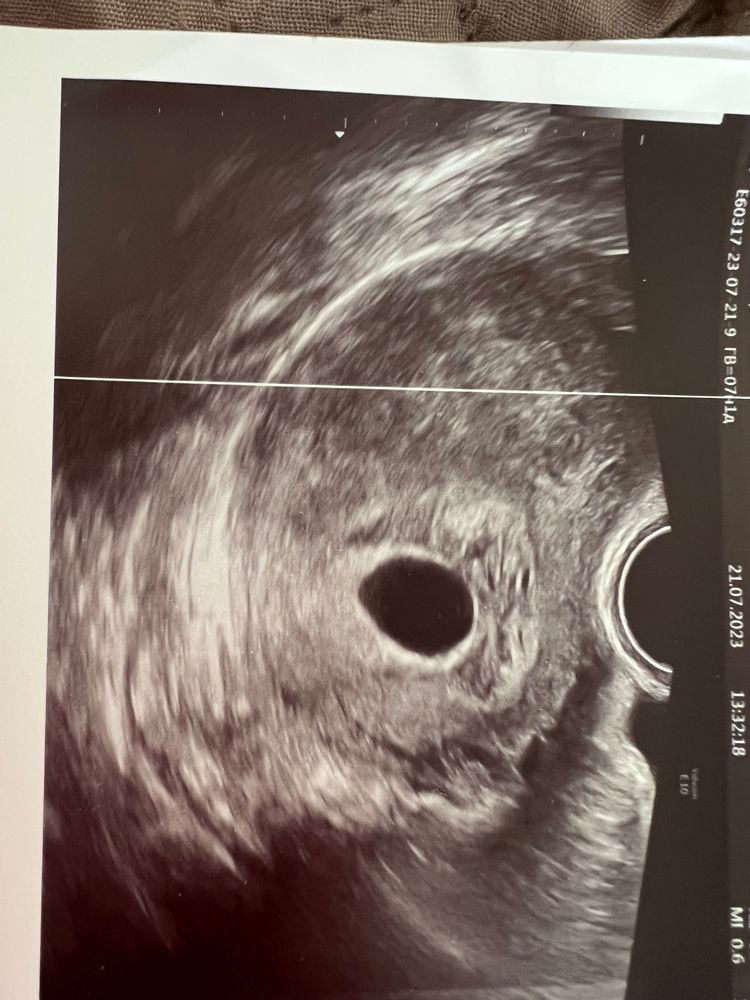

Девочки , 21 июля поставили анэмбриония два разных врача и два узи, 17 июля хгч был 19000 , на фото последнее узи,срок 7 акушерских недель , жм не видят , хотя был за неделю до этого, направили на чистку , смирилась , отменила утрожестан , в надежде что начнётся отслойка , прошло три дня и тишина , ни намёка на мес , подскажите своё мнение кто что думает, одна труба,опрированная , была внематочная и замершие на ранних сроках

Диана, я нашла ваши посты месячные 1.06 значит срок у вас акушерский 7,4 уже,и овуляция не поздняя на 29 д.ц хгч -171,что соответствует 14-15 дпо,т.е овуляция была на 14-15 д.ц,на таком сроке пя 25 мм и больше и жм и эмбрион 12-13 мм с сб,у вас в заключении даже написано пя соответствует 6,2 и больше ничего,хотя УЗИ вы 21.07 делали,но сути не меняет 7,2 акушерских это большой срок уже

Если эмбрион не появится при размере ПЯ 20+ мм, то увы...

А у Вас по УЗИ размер ПЯ пока что 18 мм. Стоит переделать УЗИ ещё раз.